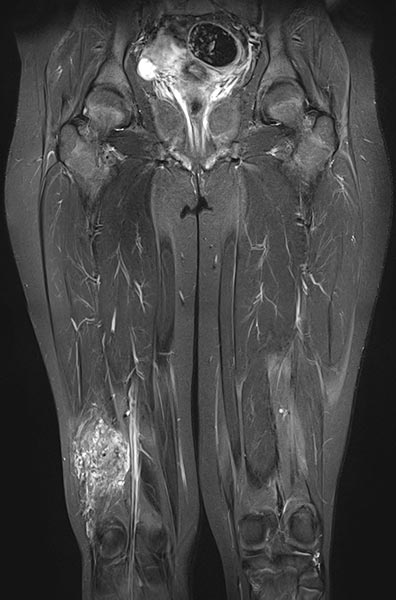

Die axiale T2-gewichtete MRT, fettunterdrückt, zeigt die nahe Lagebeziehung zum Periost des Femurs. Diese Lage ist besonders schmerzhaft durch entzündliche Reizung des Periosts.

Die T2-gewichtete MRT ohne Fettunterdrückung in axialer Schnittführung offenbart den entzündlichen, fibrotischen Umbau der Läsion durch multiple Entzündungen. Der rechte M. vastus lateralis des M. quadrizeps femoris ist komplett durchsetzt.